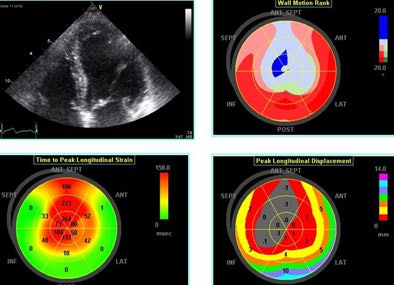

Still, "strain is more than just a number, it's a complex mathematical tensor that linear components that stretch in three dimensions," Thomas said, including linear strain and sheer strain, which can be followed by monitoring clusters of speckles. In one example, low-level exercise showed an increase circumference of strain in a normal volunteer from -16% to -25%. "This can now be integrated in three planes to give us the wall motion rank," Thomas said. Greenberg et al demonstrated that the Doppler-derived myocardial systolic strain rate is a strong index of LV contractility (Circulation, January 2002, Vol. 105:1, pp. 99-105).

![]() |

| Echo software demonstrates (clockwise from upper right) wall motion rank, time-to-peak longitudinal strain and peak longitudinal displacement in a patient with an LAD infarct. |

Left ventricular torsion is a potentially important measurement that can be performed with 2D speckle tracking, or with Doppler tissue imaging per Notomi et al, whose results were well-correlated to MRI measurements (Circulation, March 8, 2005, Vol. 111:9, pp. 1141-1147).